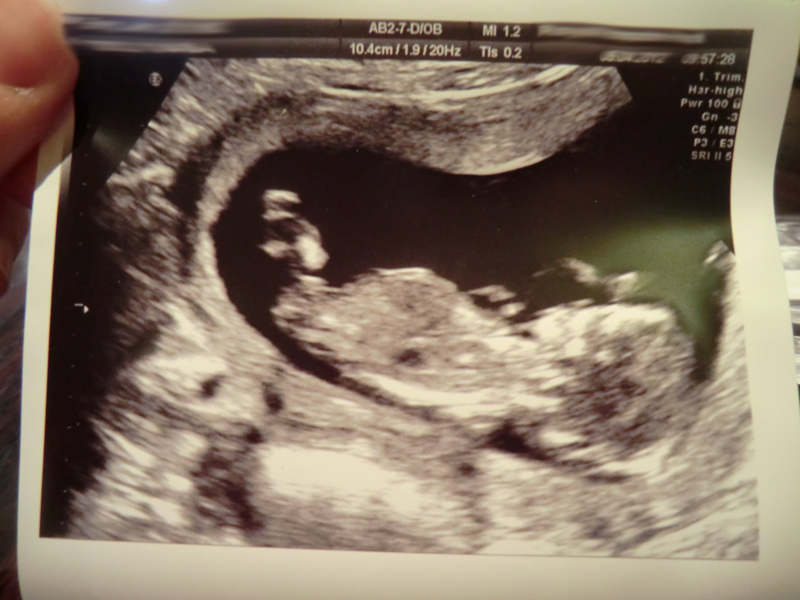

Baby had his/her legs crossed the entire time, and kept bringing it up to their chest... also the angle wasn't quite right so it was hard to see a nub and I can't be definite I saw one at all during the scan (saw it so easily with DS) although it looks like there might be a nub in these pictures.

Attachment 1916